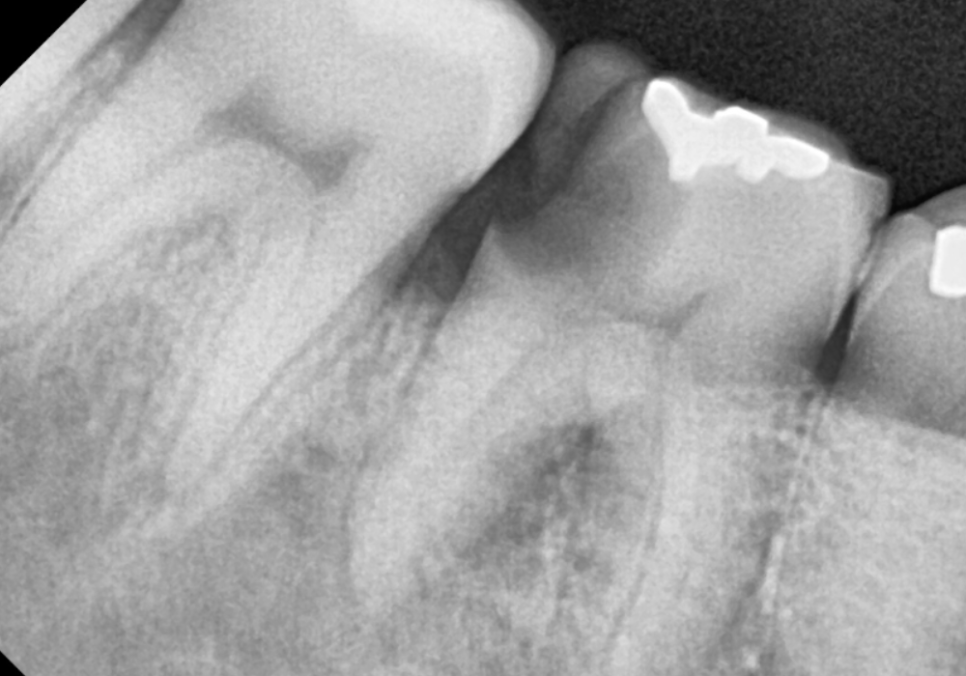

얼마 전 오른쪽 아래 어금니 통증으로

내원하신 환자분이 계셨어요.

입안을 자세히 살펴보니,

어금니(#46)의 윗면이 깨져,

그 틈으로 음식물이 꽉 끼어 있었어요.

음식물에 눌려있던 잇몸은 빨갛게 부어올라

살짝만 건드려도 피가 날 정도였어요.

엑스레이와 3D CT로

정밀 검사를 진행해 보니,

치아 사이에서 시작된 충치가

치아 내부 상아질을

이미 광범위하게 녹인 것을 확인할 수 있었습니다.

그 뿐만 아니라, 뿌리 끝에 까~맣게

염증이 비춰보이네요